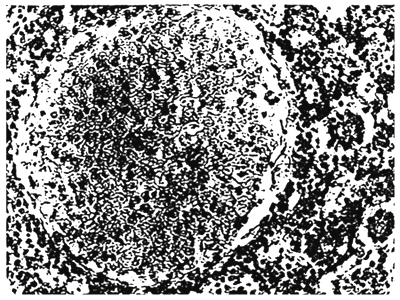

All the specimens were highly emaciated with distended abdomen and compared to healthy ones deeply pigmented. Epidermis sloughed off towards posterior region of the head, scales were raised with watery fluid filled in scale pockets, superficial ulcerations and haemorrhage on the skin at some places of the body (Fig. 1). Skin portion of the opercular flap was also found onlarged a bit. Laboratory examinations revealed emaciation, anaemia, accumulation of slight opaque fluid in the skin and the abdominal cavity, haemorrhages in the skin and pale gills. The liver was dark brown in colour. Intestine was empty with yellow mucous. Incision of the kidney resulted in the semi-fluid contents dripping out. In one such specimen posterior chamber of the swim bladder was found collapsed, twisted and thickened and had a narrow bore with little air and fluid in. Squash preparations of the kidney of infected carps showed the presence of cysts and numerous myxosporidian spores with various developmental stages. Kidney impressions stained with Gram's stain showed the presence of myxosporidian spores as well as numerous rod shaped gram-negative bacteria. Gram stained smear preparations of fluid from abdominal and swim bladder cavities demonstrated presence of myxospiridian spores and gram-negative rods. Excessive pigment accumulation was found in the liver parenchyma causing extensive damage due to pigment infilteration throughout the liver madd. Marked chordal disarray was also noticed. Myxosporidian cysts showed its presence in kidney sections and degeneration and necrosis of tubular epithelium was also prominent (Fig. 2). Areas of haemorrhage showing inflamatory process in the kidney tubules were also observed. Marked epithelial proliferations was found in the posterior chamber of the swim bladder and at some points the epithelium has thickened and has become multilayered in one specimen.

Fig. 2 Myxosporidian cyst in kidney section